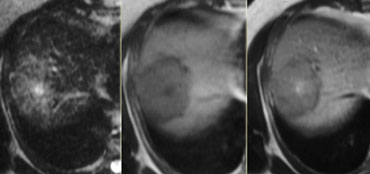

T2WI, T1WI without Gadolineum and a delayed phase after Gadolineum. T2WI, T1WI without Gadolineum and a delayed phase after Gadolineum.

If you look at the images on the left and just would consider the T2W-images, what could be the cause of the central area of high signal?

The most common cause would be central necrosis in a tumor.

However if you look at the delayed phase, you will notice that this area enhances.

So this is fibrotic tissue and the diagnosis is FNH.

Fibrolamellar carcinoma (FLC) has a dark scar on T2WI and FNH has a brigth scar on T2WI in 80% of the cases.

This means that at times the differential between FNH and FLC will not be possible.